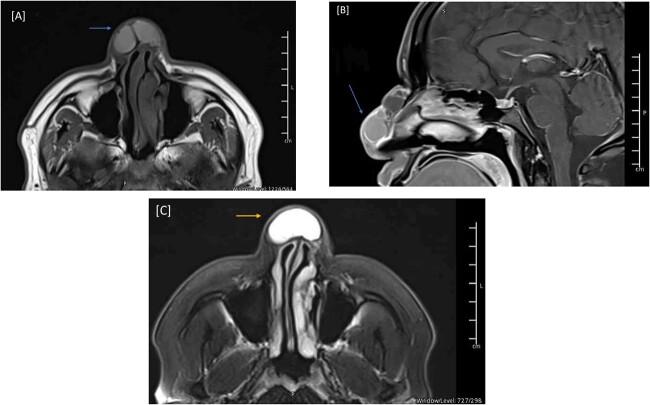

Congenital nasal masses are very rare presentations. Among these masses is a mucous cyst, which might be considered either a congenital or an acquired mass. Our report presents a case of recurrent dorsal nasal swelling that was initially managed with an open rhinoplasty. However, 1 year after the surgery, the swelling started to grow rapidly, and the patient presented with a disfigured nose. We scheduled the patient for the excision of the dorsal nasal swelling and reconstruction using the dorsal nasal flap approach. Several surgical techniques have been performed and published in the literature; however, this is the first time the dorsal nasal flap technique is being reported as a surgical approach to dorsal nasal mucous cysts. While mucous cyst formation might be congenital, the majority occur after rhinoplasty surgery. However, they can be prevented by minimizing unnecessary trauma during the surgery and ensuring the thorough removal of all epithelial tissue and foreign bodies.

摘要

先天性鼻腔肿物是非常罕见的表现。这些肿物中有黏液囊肿,它可能被认为是先天性或后天性肿物。我们的报告展示了一例复发性鼻背肿胀病例,最初通过开放式鼻整形术进行处理。然而,手术后1年,肿胀开始迅速增大,患者出现了鼻子畸形。我们为患者安排了鼻背肿胀切除及采用鼻背皮瓣法进行重建的手术。文献中已经报道了几种手术技术;然而,这是首次将鼻背皮瓣技术作为鼻背黏液囊肿的一种手术方法进行报道。虽然黏液囊肿的形成可能是先天性的,但大多数发生在鼻整形手术后。然而,可以通过在手术中尽量减少不必要的创伤并确保彻底清除所有上皮组织和异物来预防它们。